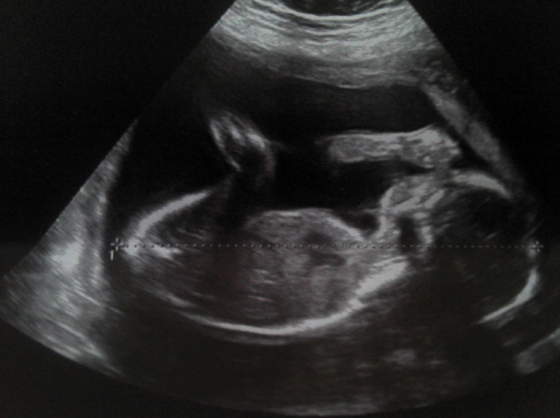

Pajka pewnie masz racje z tym ze mi w szpitalu przy usg jak miał lekarz robic i zapytałam go czy normalne czy dowcipne to powiedzał mi ze na dopochwowe to za wysoka ciaza, zreszta mało wazne jak wazne ze to kontroluja i w pore wyłapuja .A u mnie pewnie duza role miały te zabiegi i to ze brzucholek mi sie czesto napinał bo dzwigac nie dzwigałam , jutro mam wizyte zobaczymy co mi powie .A za tydzien połowkowe normalnie nie moge sie doczekac.Jestem chyba jedna z niewielu ktora płci nie zna